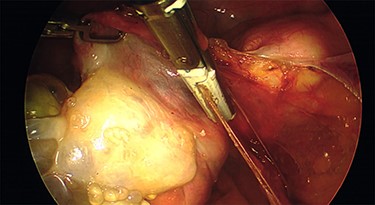

Intraoperative findings were inconsistent with all pre-operative ultrasound diagnoses. Both ovaries appeared suspicious for malignancy with cystic lesions covering the surface of the right, while the left appeared to contain two smaller cysts (Figs 3–5). There were no hydrosaplinges or free fluid within the pelvis. Given the abnormal features of the ovaries, the surgeon proceeded with the laparoscopic BSO without spillage. Pelvic washings were performed, though there were no atypical peritoneal or omental lesions for biopsy.

The intra-operative photographs of the posterior aspect of the right ovary.